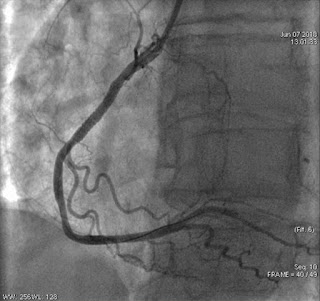

Правая коронарная артерия

Хорошо виден стеноз и заполнение правой коронарной артерии и ее ветвей ниже него.

Левая коронарная артерия - интактна.

Посмотрите на "портрет" правой коронарной артерии после стентирования: отлично проходимая артерия, кровоток TIMI 3 и TMPG 3. Посмотрите еще раз на ПКА ДО стентирования и попробуйте найти разницу (кроме стента, конечно :).

Чтобы облегчит задачу, я расположил обе ангиграммы бок о бок. ПКА до стентирования - слева, после стентирования - справа.

Зелеными стрелками отмечен стеноз ПКА, желтыми - стент в просвете артерии (если присмотритесь, то он даже виден), красными стрелками отмечены две артерии в зоне стентирования, это - конусные КА, одна из них - более крупная. Обратите внимание - эти артерии имеются ДО стентирования и их НЕТ после!Полный протокол ЧКВ: